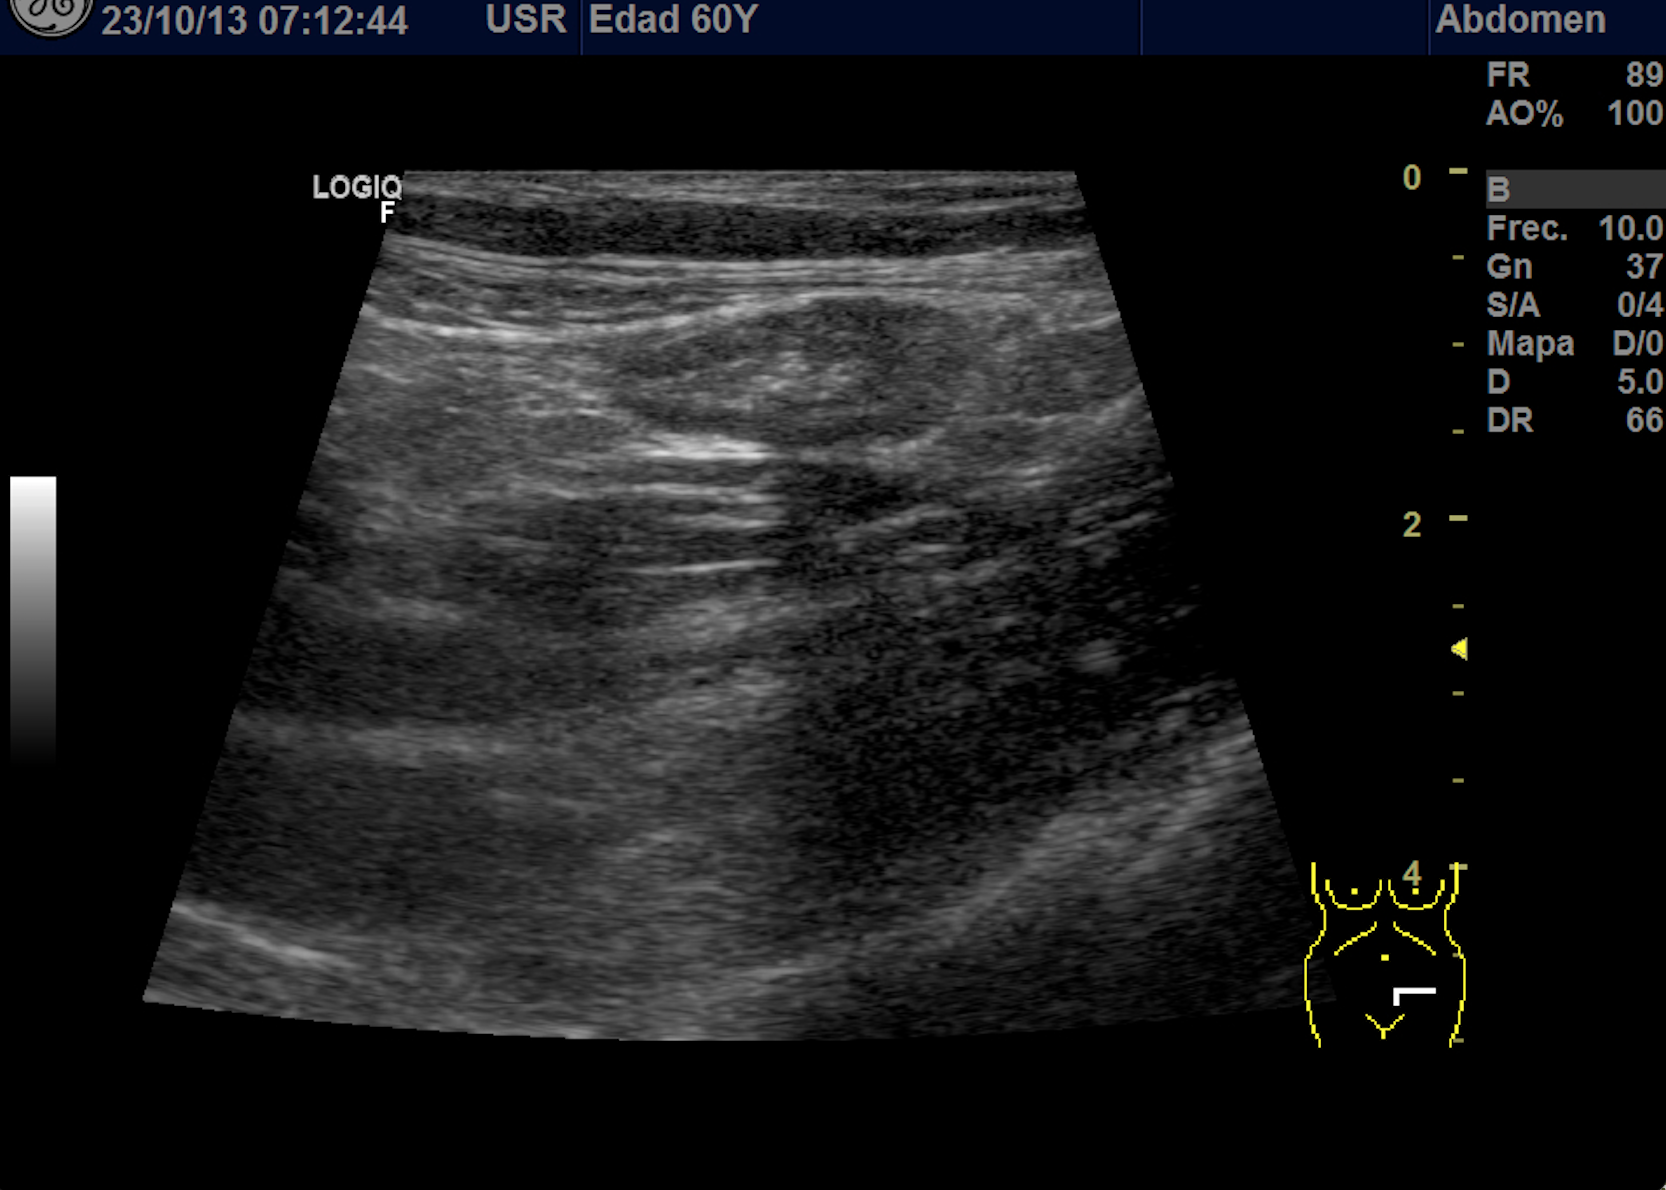

También se realiza ecografia en urgencias del hospital.

En el hospital se realiza una nueva ecografía en el servicio de radiología confirmando el diagnóstico de sospecha: diverticulitis aguda en sigma distal sin datos de complicación. Hinchey 1A.